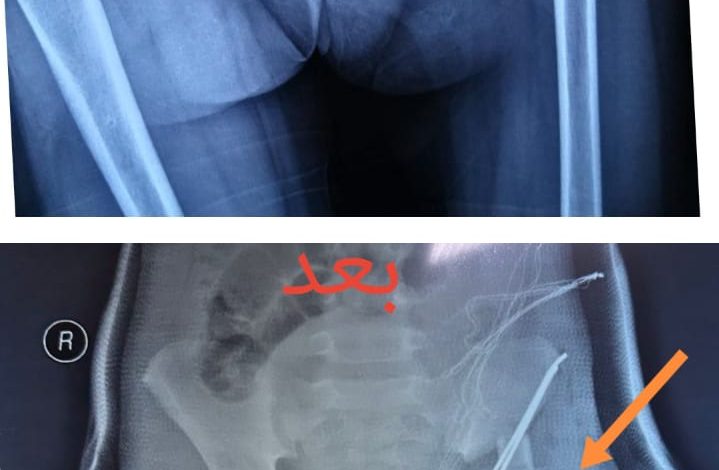

في عملية مُعقدة إستمرت 4 ساعات .. إعادة خلع ورك لطفلة كربلائية عمرها سبعة أعوام

نجح فريق طبي وصحي مُختص بجراحة العظام والكسور في مدينة الإمام الحسين (ع) الطبية بكربلاء المُقدسة ، في إعادة خلع الورك الولادي لطفلة بعمر سبعة أعوام بعملية ناجحة ، فيما كانت الحالة مُعقدة لتأخر إجراء تلك العملية بوقتٍ مُبكر ، وقال الطبيب المُختص الدكتور ضرغام حسن المسعودي ، إن ” الطفلة كانت تعاني بسبب عرجة شديدة نتيجة خلع مفصل الورك ، والذي بدوره سبب لها مُعاناة في المشي وسيتسبب مُستقبلاً في حال عدم علاجه في آلام مُزمنة وخشونة مُبكرة ” ، واصفًا تلك الحالة بأنها مُعقدة لكون أنه لم تُجر لها عملية إعادة الخلع بوقتٍ مُبكر “. وأضاف أنه ” عقب إجراء الفحص الطبي والشعاعي اللازمة وتهيئة مُتطلبات عملية التدخل الجراحي لإعادة خلع الورك لدى الطفلة بالشكل المطلوب ، حيث إستمرت العملية 4 ساعات تم خلالها قص أعلى الفخذ ، وإرجاع الخلع مع قص وتدوير الفنجان ، ووضعها في جبس بنطلوني لمدة ( 3 ) أشهر ” ، مُبيناً أن” الطفلة تحضى برعاية وعناية كافية عقب العملية في ردهة الجراحية نساء لحين مُغادرتها المدينة الطبية ” ، وشارك في إجراء العملية ونجاحها فريقاً ضم عدداً من الملاكات الطبية والصحية”.